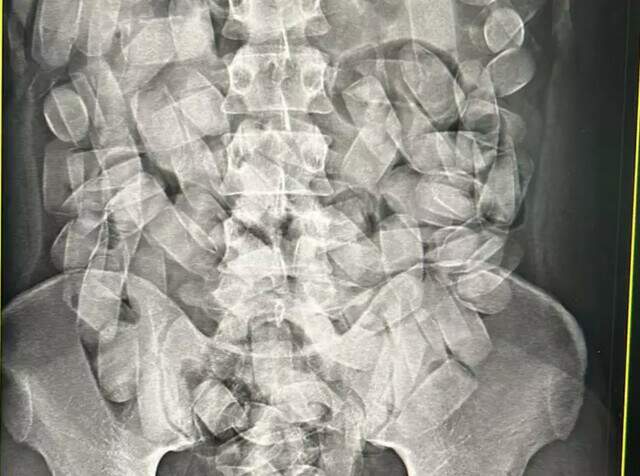

A presença da droga no estômago do passageiro foi detectada pelo raio-x. Nesta semana, essa foi a segunda prisão em flagrante por tráfico de drogas no aeroporto de Corumbá.